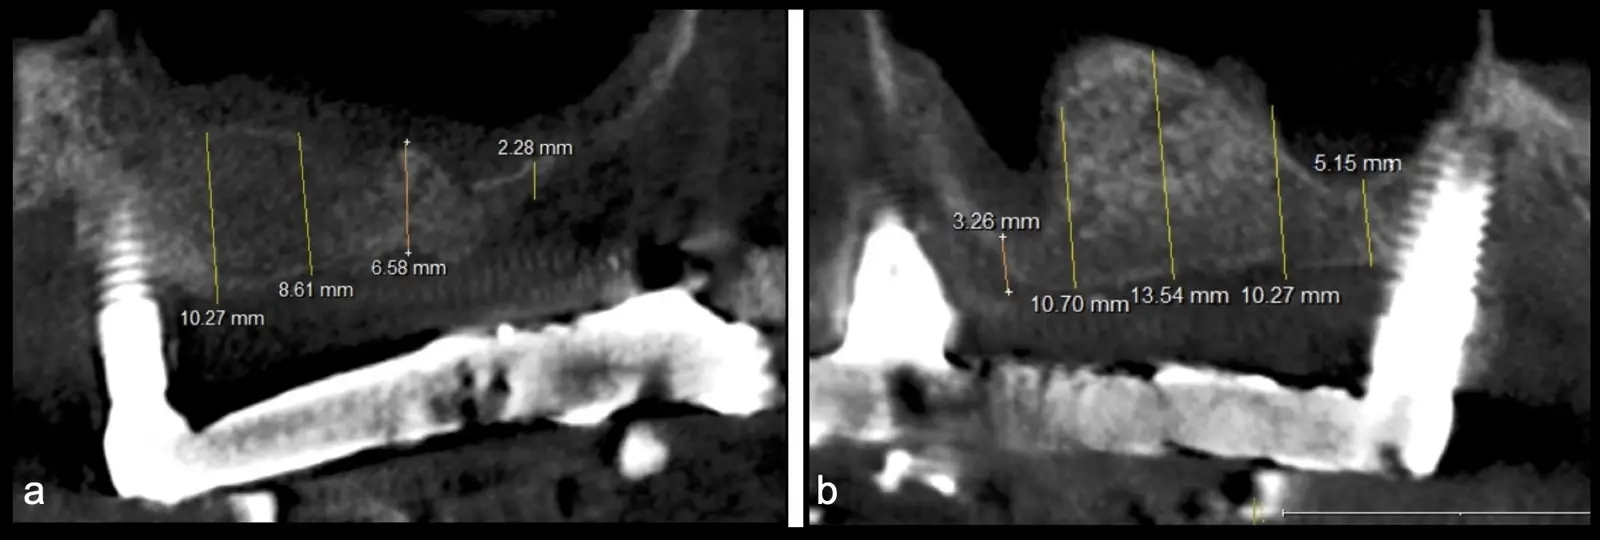

El levantamiento de piso de seno maxilar es una técnica quirúrgica aceptada previa o simultáneamente a la colocación de implantes dentales. La mayor evidencia científica refiere que si se tiene entre 0 -7 mm de altura ósea se debe realizar la elevación sinusal junto con injertos óseos; y a partir de los 8 mm, se hace más predecible la colocación simultánea de implantes dentales.1-3

Aunque esta técnica es predecible, la perforación de la membrana sinusal es la complicación intraoperatoria más común, con una prevalencia de hasta el 58.3%.4 Existen también otras complicaciones reportadas, como hemorragias asociadas a la lesión de la anastomosis arterial en el área de la pared lateral del seno maxilar.5-8

El tipo de inserto a ser utilizado dependerá del espesor de la pared ósea. Si la pared es menor a 0.5 mm, es mejor utilizar insertos de desgaste para prevenir la ruptura de la membrana de Schneider; si el espesor es mayor a 0.5 mm, se puede utilizar insertos de corte de espesor medio (Figura 3).

El clínico puede retirar la tabla ósea o introducirla como “tienda de campaña” dentro del seno maxilar. En cualquiera de las alternativas, es importante evaluar la presencia de tabiques óseos y de la arteria postero alveolar superior.